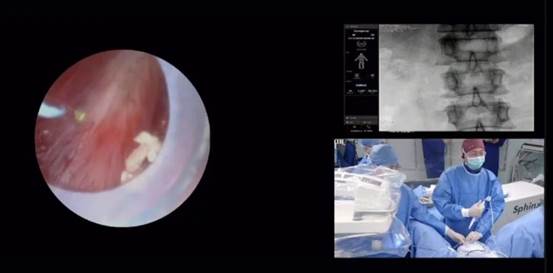

作为国际尿石症联盟主席兼秘书长、本次培训的东道主,曾国华教授进行了理论授课和现场实操。期间有学员问及:“  有什么技巧可减缓长时间手术引起的肩膀 疼痛?”曾教授回应首先是选用镜身轻好握持的一次性输尿管软镜,其次在执行手术时处于坐姿,同时左手肘可用手术床的腿架支撑

自疫情回暖后首次夏季开班就吸引了来自希腊、德国、西班牙、比利时、澳大利亚等 22 个欧洲及亚太国家的多位年轻泌尿科医生齐聚希腊帕特雷大学会议中心。除了干货满满的泌尿大师讲座和精彩的手术教学展示,还有手把手操作实践( Hands-on training )培训环节,医师学员分为四组轮换上手并热情投入到模拟操作 f-URS 碎石手术中。

瑞派旗下泌尿产品良好的操控性能,清晰的主机图像,加上强大的系统抗干扰性可帮助医生在激光碎石手术达到更佳效果。